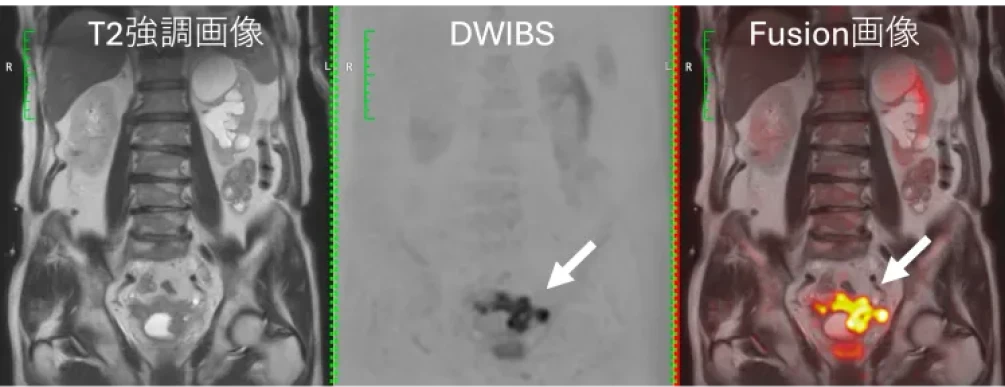

高原クリニック イノベーティブスキャンのMRIは、すい臓がんの早期発見において高精度な診断を実現しています。